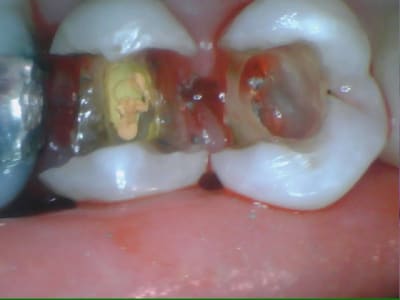

Inlay réalisable sur 24 et 34 ?

Est-ce que le collage suffirait à maintenir les parois ?

Le choix thérapeutique pris a été très classique.

Arnaud Go écrivait:

> Onlay réalisable sur 24 et 34 ?

oui

> Est-ce que le collage suffira à maintenir les parois ?

non, je préférai les recouvrir sur 1.5 mm par l'onlay